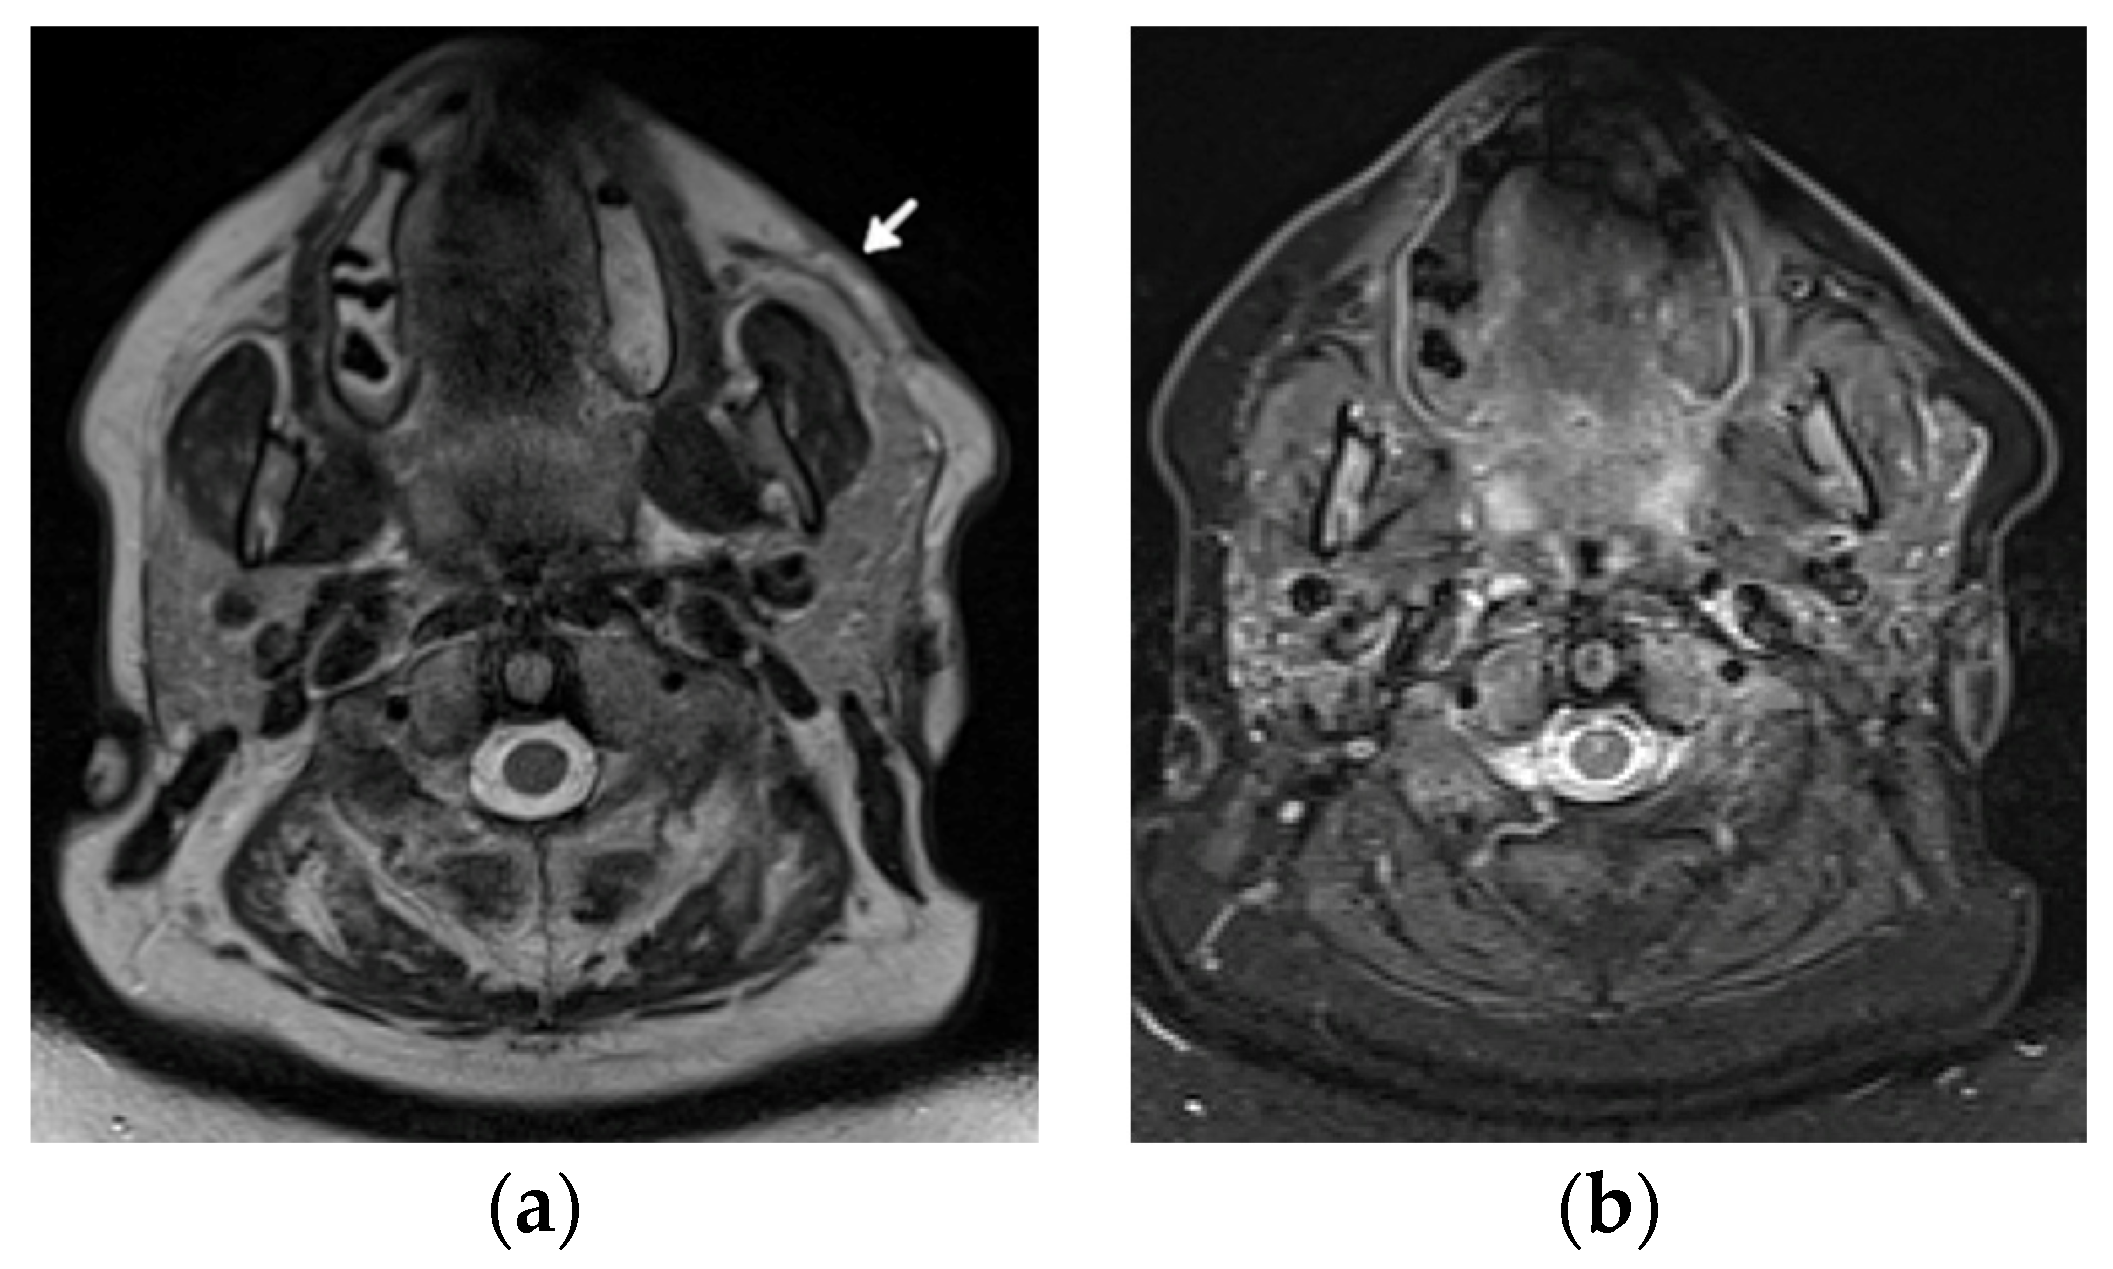

The imaging features of facial LP are extremely scarce in the literature (Figure 10).

Figure 10.

A 48-year-old female patient with systemic lupous erythematosus and a long history of lupus panniculitis and post-inflammatory atrophy of the subcutaneous tissues of the left cheek without active inflammation (arrow), seen in (a) the axial T2-weighted time spin echo and (b) T2 turbo inversion recovery magnitude MR images.

US will likely show inflammatory changes and hyperemia along the involved and surrounding subcutaneous adipose layer. However, the main role of US is to exclude an underlying abscess, drainable fluid collection, or mass.

If US is unrevealing, MRI is the imaging modality of choice. The hallmark of LP on MRI is the loss of the normal T1 bright signal within the subcutaneous adipose layer. In active stages, a high signal intensity is seen on the fluid-sensitive sequences with bright, hazy enhancement on the post contrast T1-weighted images with fat saturation. It is important to distinguish LP from lymphoma, which unlike LP, does not track along the fatty tissue planes.